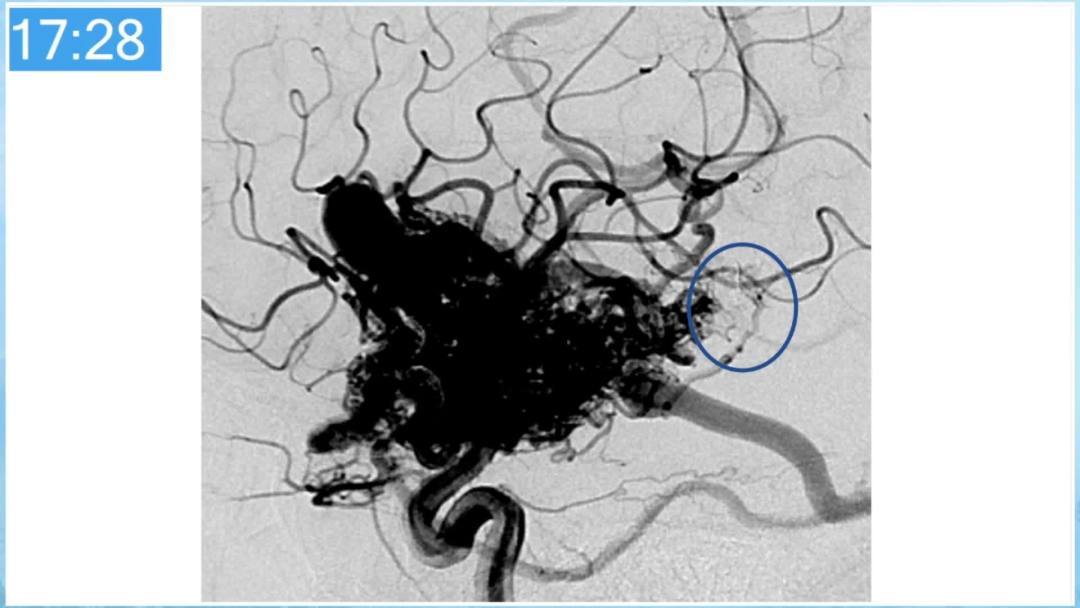

合理的复合平台下的综合治疗,针对每一个病变对应不同方法安全性分析,不预设、不排斥,每种技术发挥到最佳,互相保障。

本期为大家特别分享:空军军医大学唐都医院邓剑平教授的精彩会议内容《颅内动静脉畸形的复合手术治疗》,欢迎大家阅读和分享!